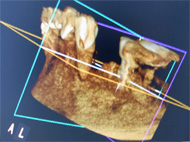

【歯科用3DCT】

3D画像では、高度歯科治療(インプラントや歯周病など)の診断に有効であり、従来のレントゲンの平面画像では難しいとされたものの確認などが行えます。

エックス線の照射時間と撮影領域を必要最小限まで抑えたレントゲンで3D撮影を行っております。